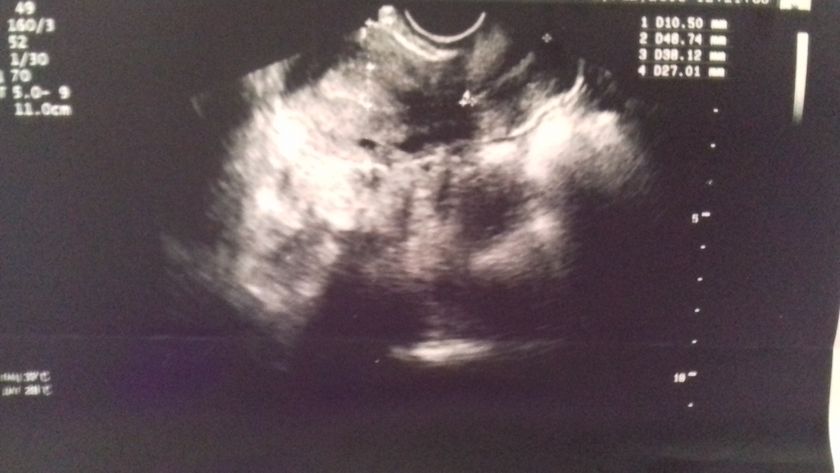

Вчера была на узи лечила поликистоз яичников.Это фото матки врач долго смотрела, я спросила она промолчала.Что за точки черные в матки ??? прошу тапки мимо.мне итак тяжело прошлый раз была беременность но на 3-4 недели выкидыш.Потом лечила поликистоз.В общем долго молчала держала в себе. На данный момент 8 дпо.тянит низ живота.

Сосуды просто.

А какое заключение по УЗИ?

Изменений не выявлено.и все

Сосуды матки

Спасибо.а то врач так долго смотрела я спросила она промолчала.